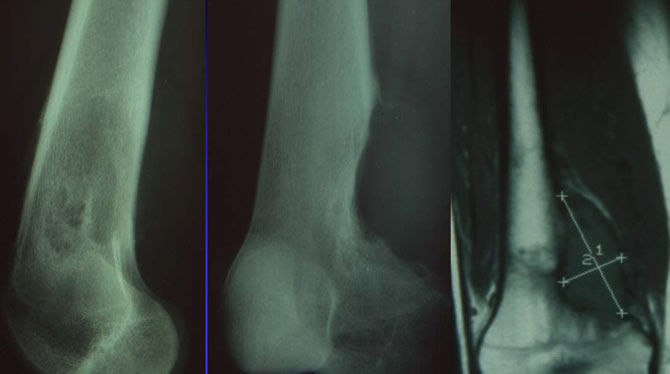

Chondosarcomes de bas degré de malignité (IA) chez une jeune femme de 22 ans.

La tumeur douloureuse depuis 3 ans a progressiement soufflé le fémur inférier et s'est propagé dans la médullaire bien au dela de l'image anormales sur les radiographies standard.

L'IRM permet de mesurer l'extension intramédullaire et de vérifier que la tumeur reste confinée a l'os.